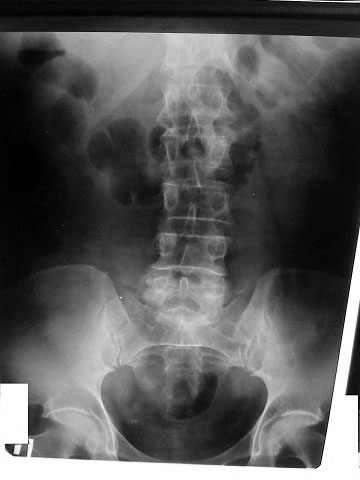

Рентгенолог сказал, что есть сдавление правого мочеточника извне на уровне с\3. Снимки не видела. Думаю, после обеда смогу их увидеть и выложить. Хочу её после обеда, как освободится аппарат, пересмотреть.

средней трети мочеточника

Сори за задержку- технические трудности.

Вот снимки: